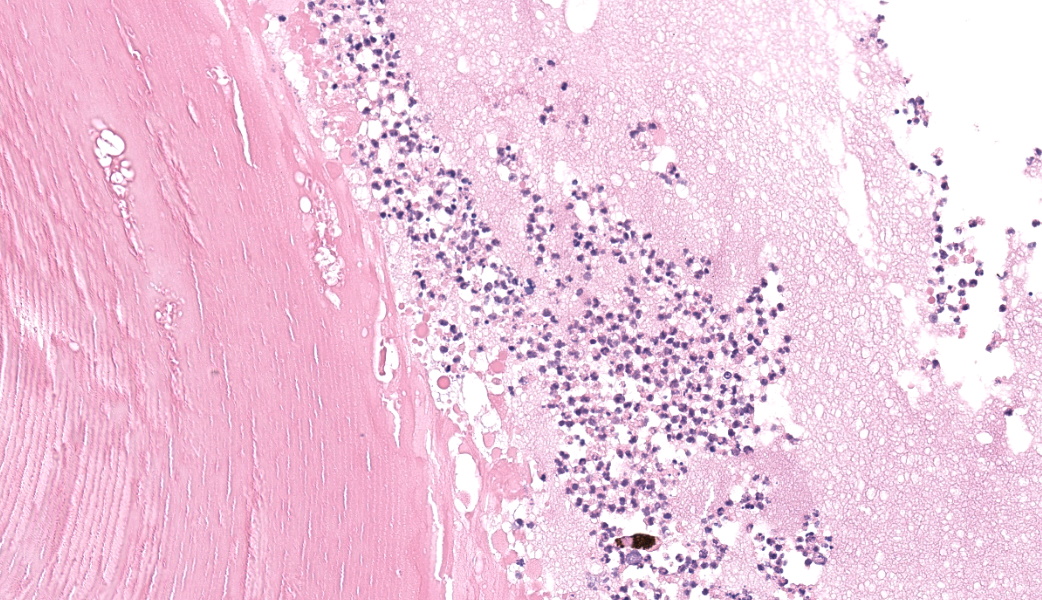

Filling all ocular chambers and coating the surfaces of intraocular structures are vast accumulations of exudate consisting of myriad degenerate and intact neutrophils, many macrophages, abundant amounts of fibrinous to proteinic material, abundant necrotic cellular debris, occasional pools of extravasated erythrocytes, and multifocal colonies of mixed bacteria (rods and coccobacilli). Centrally incorporated into the inflammatory exudates is a ruptured lens which lacks a capsule in many areas and has highly undulating free capsule margins regionally. The lenticular stroma is variably vacuolated with the following features: streaks of pallor, Morgagnian globules, many infiltrating leukocytes (mostly neutrophils), and occasional pockets of similar bacteria. The retina is diffusely detached and largely inapparent apart from remnant segments of atrophied and degenerate retina enmeshed within the exudate. Suppurative to pyogranulomatous inflammatory infiltrates multifocally extend into the iris, ciliary body, choroid, optic nerve which is significantly gliotic with rarefied neuropil, and optic nerve meninges. The iris is displaced anteriorly and multifocally abuts the posterior aspect of the cornea. The anterior chamber is severely narrow, and the drainage angle is collapsed and inapparent. The corneal stroma is moderately to markedly oedematous and contains small to moderate numbers of scattered neutrophils. The anterior corneal epithelium appears attenuated in areas. The sclera is variably thinned with multifocal often perivascular infiltrates of lymphocytes and plasma cells with variable numbers of admixed neutrophils and occasional macrophages. There are increased numbers of perilimbal pigmented cells. A thin to moderately thick layer of oedematous and inflamed granulation tissue regionally lines the mid and posterior scleral margins outside the globe and extends into a bundle of periocular skeletal muscle. In addition to infiltrates of the aforementioned inflammatory cells, the granulation tissue also contains many golden-brown pigmented macrophages (siderophages) which are concentrated at the level of the ciliary body. There is abundant haemorrhage in the retrobulbar loose connective tissue.Contributor's Morphologic Diagnoses:

Talk about a descriptive case that made, for obvious reasons, an excellent sales pitch on why pathology is the best profession! This case provides an excellent opportunity for participants to push themselves on their ocular descriptive abilities. Many thanks to this contributor for a fantastic case! Much like the previous eye case in this conference, there was substantial discussion on ocular pathology. The most informative nuggets from that conversation included utilizing the lens capsule, which is an easily identifiable structure in the eye, to assist with orientation in a busy ocular slide such as this one. The pigmented irideal stroma, as well as the “golden” fibers of the iris, can also be used to help identify structures that might otherwise be difficult to ascertain due to the degree of damage and/or inflammation.This case had beautiful examples of iris bombe (iris pushed forward into the anterior chamber and adhered to the back of the cornea), numerous types of fibrovascular membranes (retrocorneal, preiridial, cyclitic, etc.), and a fantastic phakoclastic panuveitis from lens rupture. The six types of uveitis and their definitions were discussed and included: 1) anterior uveitis (inflammation of the iris and ciliary body), 2) posterior uveitis (inflammation of the ciliary body and choroid), 3) panuveitis (iris, ciliary body, and choroid affected), 4) chorioretinitis (inflammation of the choroid and retina), 5) endophthalmitis (inflammation of uvea, retina, and ocular cavities), and 6) panophthalmitis (all ocular structures are affected, including sclera). Being able to recognize and accurately use these terms as pathologists can provide crucial information to ophthalmologists when it comes to treating these patients.